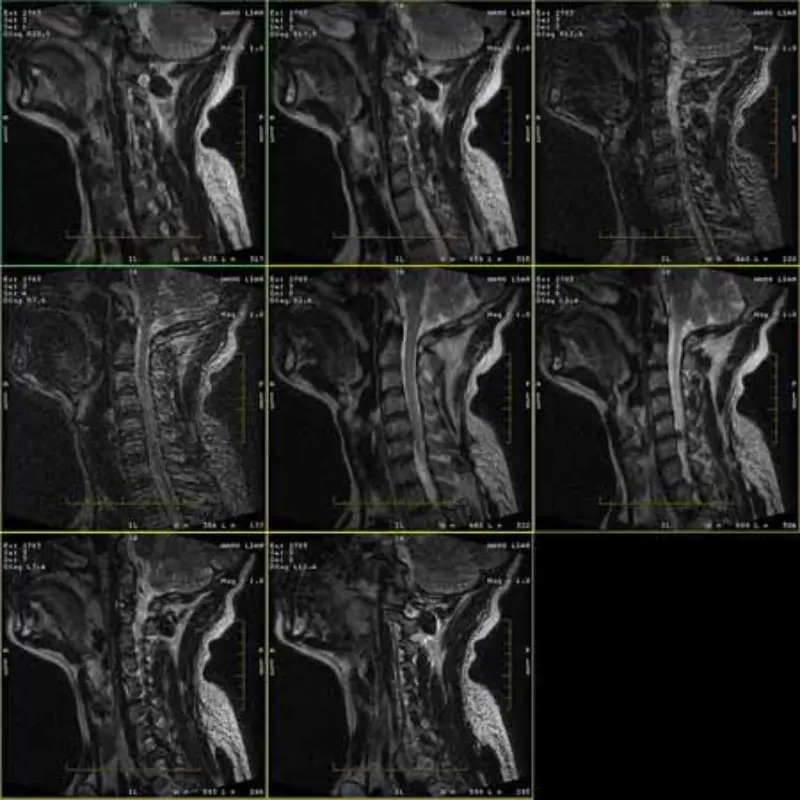

Le immagini dei protocolli FRFSE e GRE presentano immagini fantasma e talvolta in una serie compaiono immagini con SNR basso. Ma le immagini del protocollo SE sono normali.

Si prega di guardare allegare immagini.